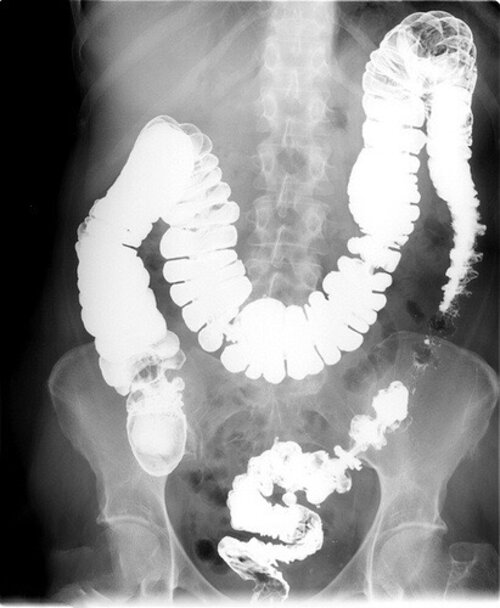

Uitați-vă la scanarea organelor unei femei care a început doar cu respirație urât mirositoare, constipație și arsuri gastrice, dar a ajuns cu un diagnostic fatal.

Cancer de colon la o femeie care s-a plâns de constipație frecventă

Această femeie nu a urmat niciun tratament real, ci doar a utilizat medicamente la întâmplare, recomandate de farmacist, cu fraza bine cunoscută: „Acesta este un produs bun pentru stomac, încercați-l!” Probabil că ați auzit ceva similar într-o farmacie din cartierul dumneavoastră.